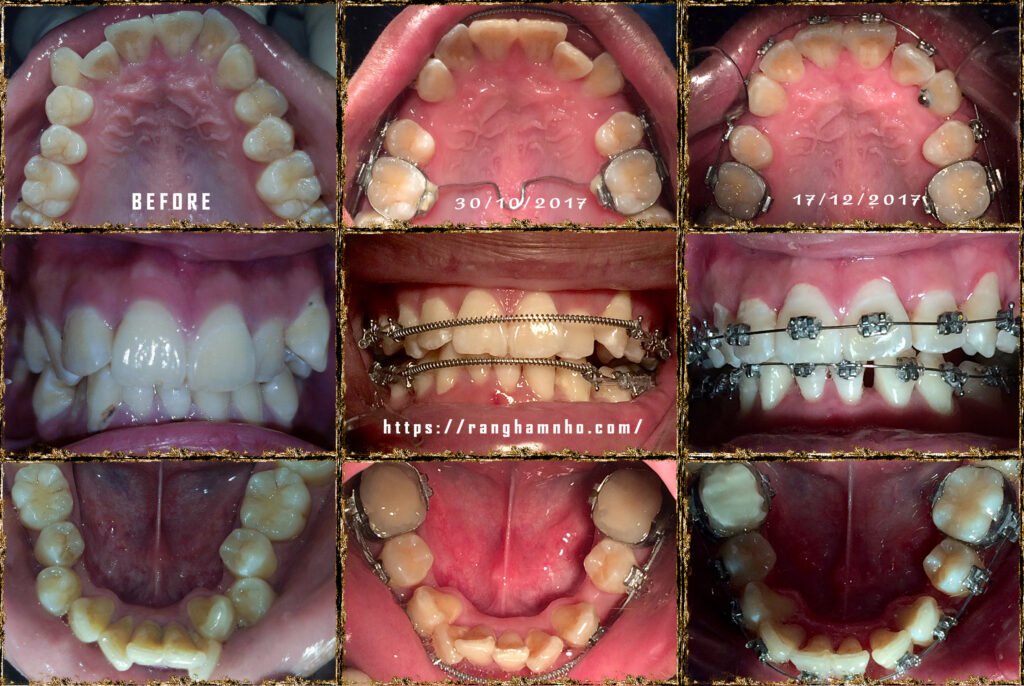

Bệnh nhân nam sinh năm 1998. Khớp cắn hạng I, với chen chúc và khấp khểnh nặng ở cả 2 hàm trên và dưới.

Cung hàm trên và cung hàm dưới đều hẹp, răng thiếu chỗ nghiệm trong.

Kế hoạch: Nhổ 4R4, chỉnh nha phân đoạn

Làm phẳng mặt phẳng cắn bằng cung tiện ích TMA 17×25 hai hàm